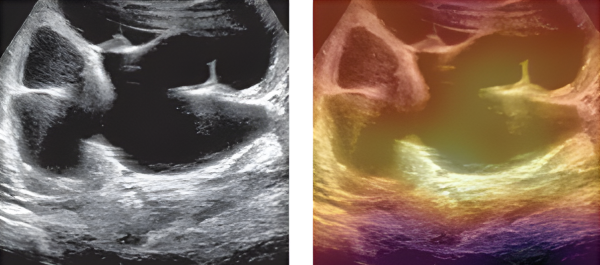

Two ultrasounds of kidneys, the image on the right is covered in a colourful layer that indicates an AI model has read it.

The left side of the image shows a kidney ultrasound as Rickard would see it. The right side of the image shows how the AI model scans the ultrasound, with the highest importance areas indicated in light yellow.